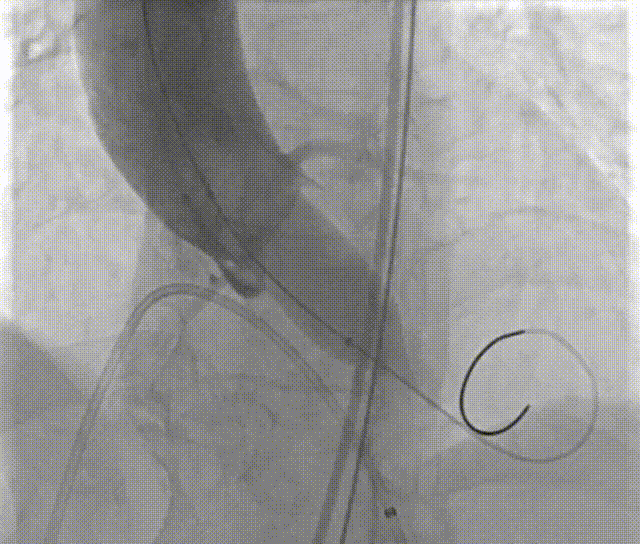

由于患者整体结构小,是这台手术最大的难点。主动脉瓣叶增厚,冠脉高度小于12mm均较低,冠脉风险极高,病情复杂。但顾及到患者整体瓣环小,即使行外科换瓣手术也是需要通过原瓣叶裁剪后扩张瓣环才能放入外科瓣,外科手术风险也很高,手术创伤大,出血多。相比之下,经导管主动脉瓣置换术(TAVR)具有手术创伤少、出血少,术后恢复快等特点,姜小飞主任通过多方面的考虑最终决定尝试实施经导管主动脉瓣置换术。经过多方专家会诊,共同评估并制定了几种可能的手术方案:1、考虑到冠脉风险,单纯球囊扩张,解决狭窄,但不排除反流增加的可能;2、如冠脉无阻挡,考虑植入瓣膜,但由于患者“4小”,不排除瓣膜出现严重移位。结合前期分析结果,最终采取先对其进行球囊的预扩张,再考虑治疗主动脉瓣狭窄的策略。但是必须采用瓣膜工作区“收腰”工艺好的“环上瓣”,以避免瓣膜工作区因为小瓣环而打不开;必须使用可回收输送系统,避免一次性释放后位置不佳,进行位置调整甚至全回收放弃瓣膜释放。经过多科室团队和启明工程师对患者病例深入分析,反复讨论后,结合患者病情复杂等因素,决定选用18mm球囊预扩张,同时决定使用VenusA-Plus可回收输送系统,选择植入L23号瓣膜经由右侧股动脉入路完成此次手术。

手术过程